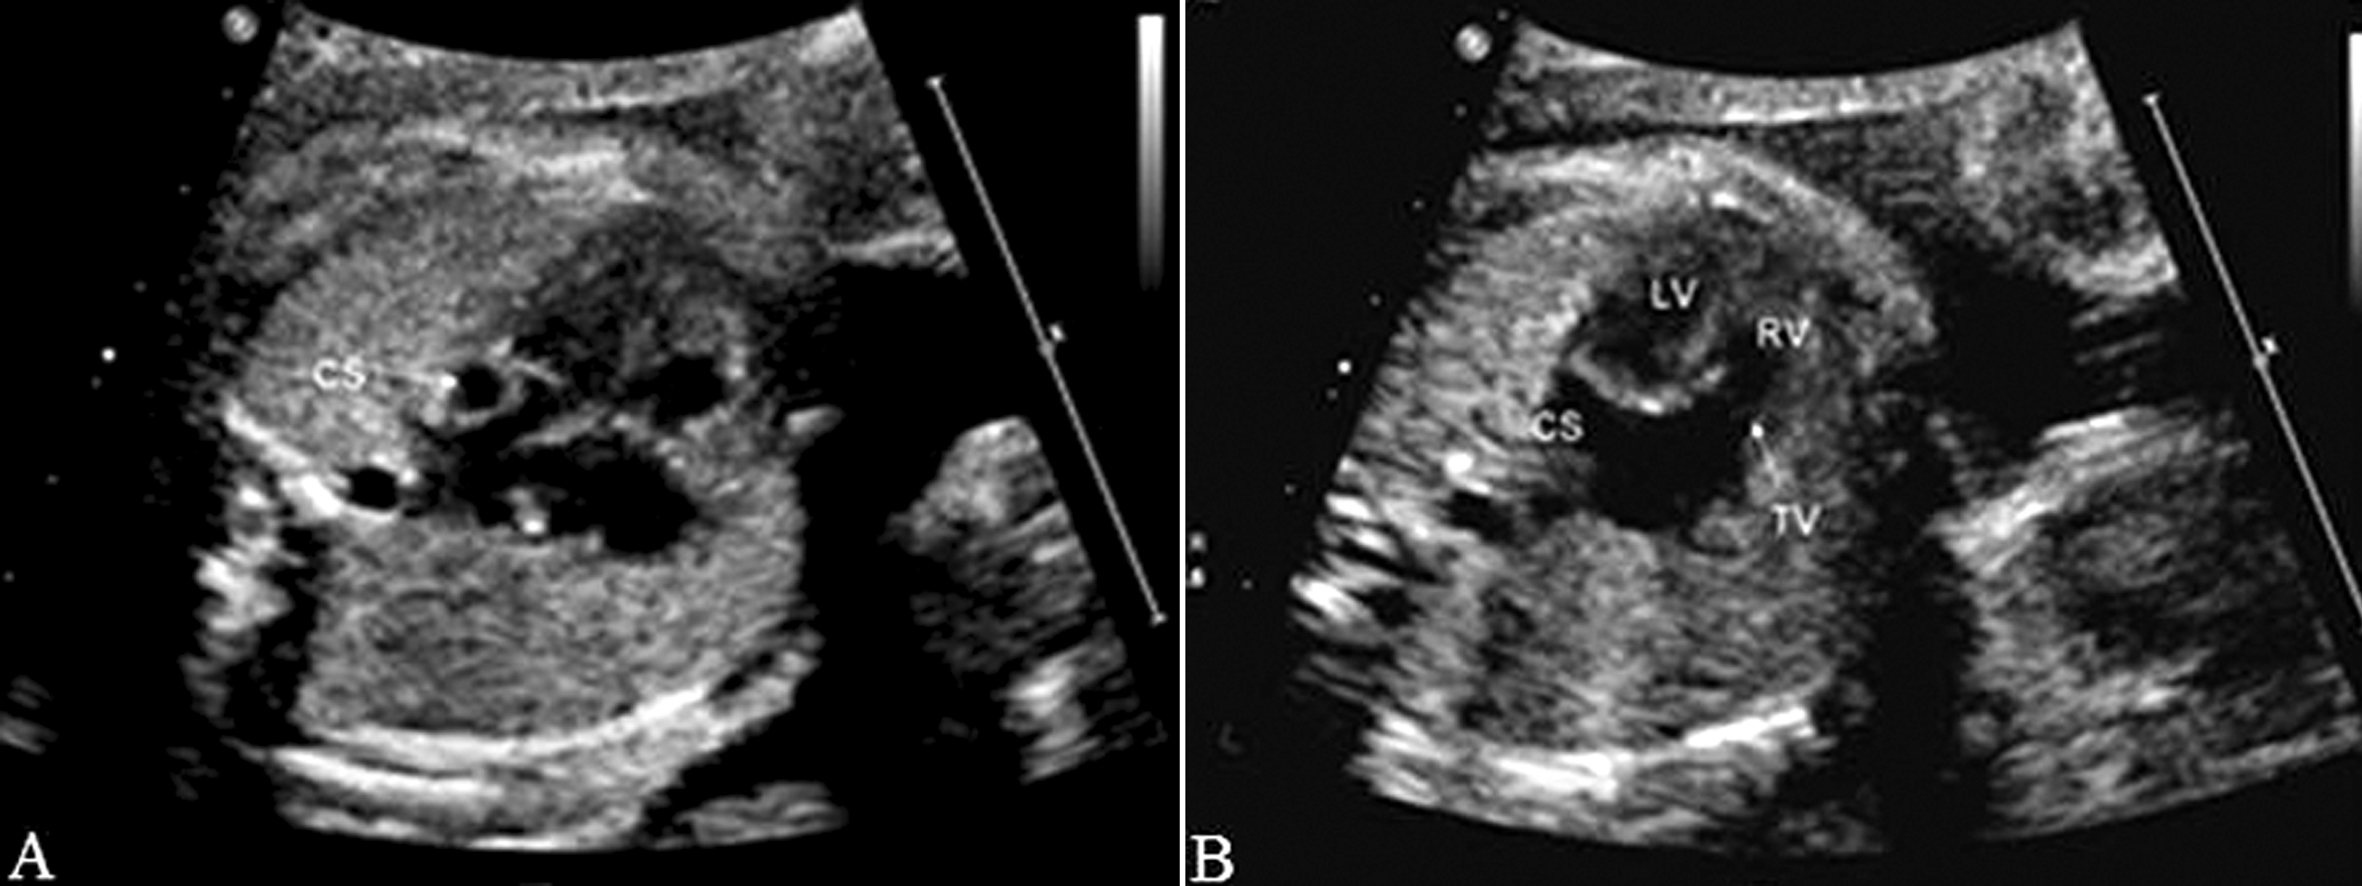

部分性AVSD超声图像特征为:房间隔的原发隔缺失,房室瓣与房室隔十字相交的正常结构消失,二、三尖瓣关闭时呈水平位,同时伴有二尖瓣和(或)三尖瓣反流,而室间隔完整,心室水平无分流(图3)。原发孔型ASD应与增大的冠状静脉窦相鉴别。前者心尖四腔切面观始终无法显示正常的十字交叉结构,后者声束在心尖四腔切面观靠后时显示等号状增大的冠状静脉窦,同时不能显示二尖瓣,而心尖四腔切面观时可见正常的十字交叉结构,并可见左侧房室沟处呈环状增大的冠状静脉窦(图4);另外,冠状静脉窦增宽常合并左侧上腔静脉永存,三血管气管切面在肺动脉左侧可见与右侧上腔静脉对称的血管即左侧上腔静脉(图5)。

图4 胎儿冠状静脉窦增宽